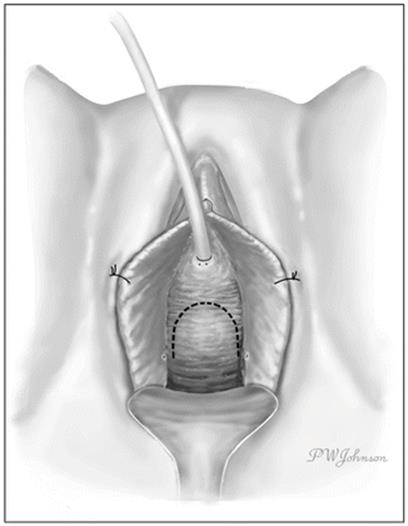

An inverted “U” is marked out along the anterior vaginal wall with the base of the “U” at the level of the distal urethra and the limbs extending to the bladder neck or beyond (Fig. 11.6). Care is taken to ensure that the limbs of the “U” are wider proximally (towards the bladder neck) to ensure adequate vascularity at the distal lateral margins of the anterior vaginal wall flap. As opposed to the inverted “T” incision, the inverted “U” incision provides excellent exposure laterally at the level of the midvagina and can be extended proximally as needed for lesions that extend beyond the bladder neck. Injectable saline can be infused along the lines of the incision to facilitate dissection. An anterior vaginal wall flap is created by careful dissection with Metzenbaum scissors in the potential space between the vaginal wall and the periurethral fascia. The use of sufficient counter-traction during this portion of the procedure is important in maintaining the proper plane of dissection. Care is taken to preserve the periurethral fascia and avoid inadvertent entry into the UD.

Fig. 11.6

An inverted U-shaped incision (dashed line) on the anterior vaginal wall (Used with permission from Rovner ES. Urethral diverticula. In: Female Urology, 3rd ed. Edited by Raz S, Rodriguez LV. Philadelphia: Saunders Elsevier; 2008)